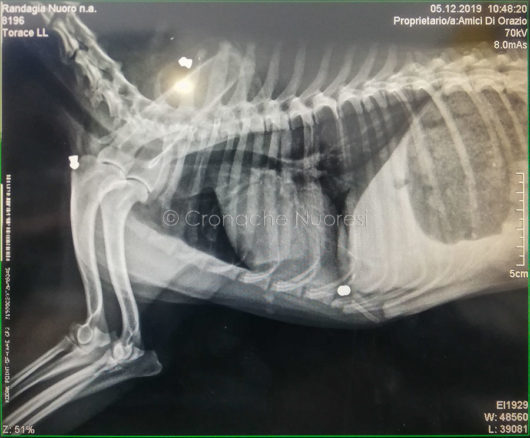

Forse per puro divertimento o per chi sa quale macabro motivo qualcuno ha infierito contro una povera e inerme meticcia, ritrovata ieri nella zona di Corte, a Nuoro, da Anna e Mario e poi affidata Amici di Orazio. Qualcuno le ha sparato addosso ben sette volte con una carabina: sei pallini sono stati riscontrati vicino alla colonna vertebrale e uno ha perforato la scatola cranica posizionandosi nel lobo frontale con la conseguenza che Funghetta (così è stata nominata la cagnetta per via della tipologia di proiettili a forma di fungo trovati nel suo corpo), ora è completamente paralizzata pur avendo ancora la sensibilità alle zampe.

«L’abbiamo trovata durante l’acquazzone di ieri sera nella stessa zona in cui fu trovato Freccia, il cane trafitto con un arpione» spiega Gabriella Manca, una delle volontarie. Il primo controllo dal veterinario ha rilevato una verità terribile: «il medico nel palparla ha sentito una specie di bozzo, dal quale, una volta inciso, è fuoriuscito il primo pallino». Questa mattina la meticcia è stata portata a Oristano, nella clinica di riferimento dell’associazione; qua è stata sottoposta ad una risonanza e a una tac dalla quale è emerso il quadro clinico sopra descritto.